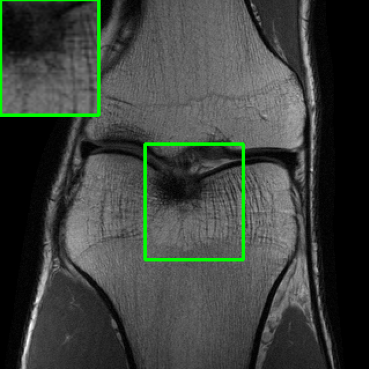

5.4 Visualizations

We now present visual samples from both the knee and brain datasets. Specifically, Figure 5 presents visual comparison of image reconstructions and their associated reconstruction errors within a closely examined region. Each image in the figure includes two inset panels in the top-left and top-right corners. The top-left inset panel, enclosed within a green bounding box, serves as a reference for the region of interest in the image. In contrast, the top-right inset panel depicts an error map in relation to the ground truth. Notably, our method stands out in its ability to capture the original image’s features, surpassing the performance of alternative methods (as also evident from the reported PSNR values). This visual comparison underscores the superior quality and accuracy of our approach in the robustification of the MRI image reconstruction task.